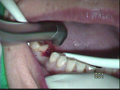

| 植牙是以純鈦或氧化鋯製成的人工牙根,植入齒槽骨中;當人工牙根與齒槽骨緊密結合後(大約三至六個月 ) ,再裝上假牙。 人工牙根就如同樁子釘入水泥中一般的穩固 ,有辦法承受相當大的咬合力 , 藉以恢復咬合咀嚼功能,更重要地是,可以保留健康的鄰近牙齒,免於被切削和骨頭不流失;也由於生物相容性高,不會破壞身體;再加上固持力強,可抓住一片骨地,讓您擁有一片天,笑容燦爛。 |

| 傳統的牙橋牙冠製作法,必需將鄰近的真牙磨小,才能 裝戴假牙。而植牙在不必破壞真牙的前提下,完成牙橋 牙冠 | ![]() |

| 生物能理念:植牙可避免傳統牙橋天然齒質被切削,防止土石流般骨質流失,恢復自信心。 上天賦予我們的、父母給予我們的任何事物,永遠是最完美、最天然的。然而,當我們不幸喪失了一顆牙時;相對的,也會流失ㄧ大片骨地;因此,本院以專精於自然醫學的立場,反對以佩戴活動假牙作為治療缺牙的方式,因其會壓迫骨頭,使骨地更流失;也反對以固定牙橋修復,因為會活生生的切削鄰近健康的牙齒。 植牙的好處 保留健康的鄰近牙齒 傳統的牙橋需修磨前後鄰牙才能裝戴假牙。(牙橋) 人工植牙不必破壞真牙便能製作固定假牙。 提供更理想的假牙設計 若缺牙數目較多,人工植牙可讓您擁有固定假牙,不需佩戴活動假牙;但若條件不足,人工植牙亦可用來支撐您的活動假牙,提供比傳統活動假牙更好的穩固性與咀嚼力量。 全口無牙時,可以人工牙根做較有咬合力較穩固之活動假牙。 |